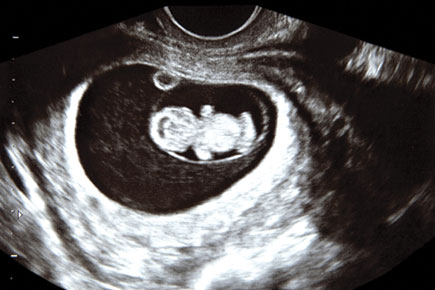

Colorado voters weighed the legal definition of “personhood,” voting on an amendment to the Colorado Constitution that would define the term “person” as applying “from the beginning of the biological development of that human being.” The Denver Post reports that the measure was failing by a 3-to-1 margin, the same as the 2008 vote on a similar amendment.